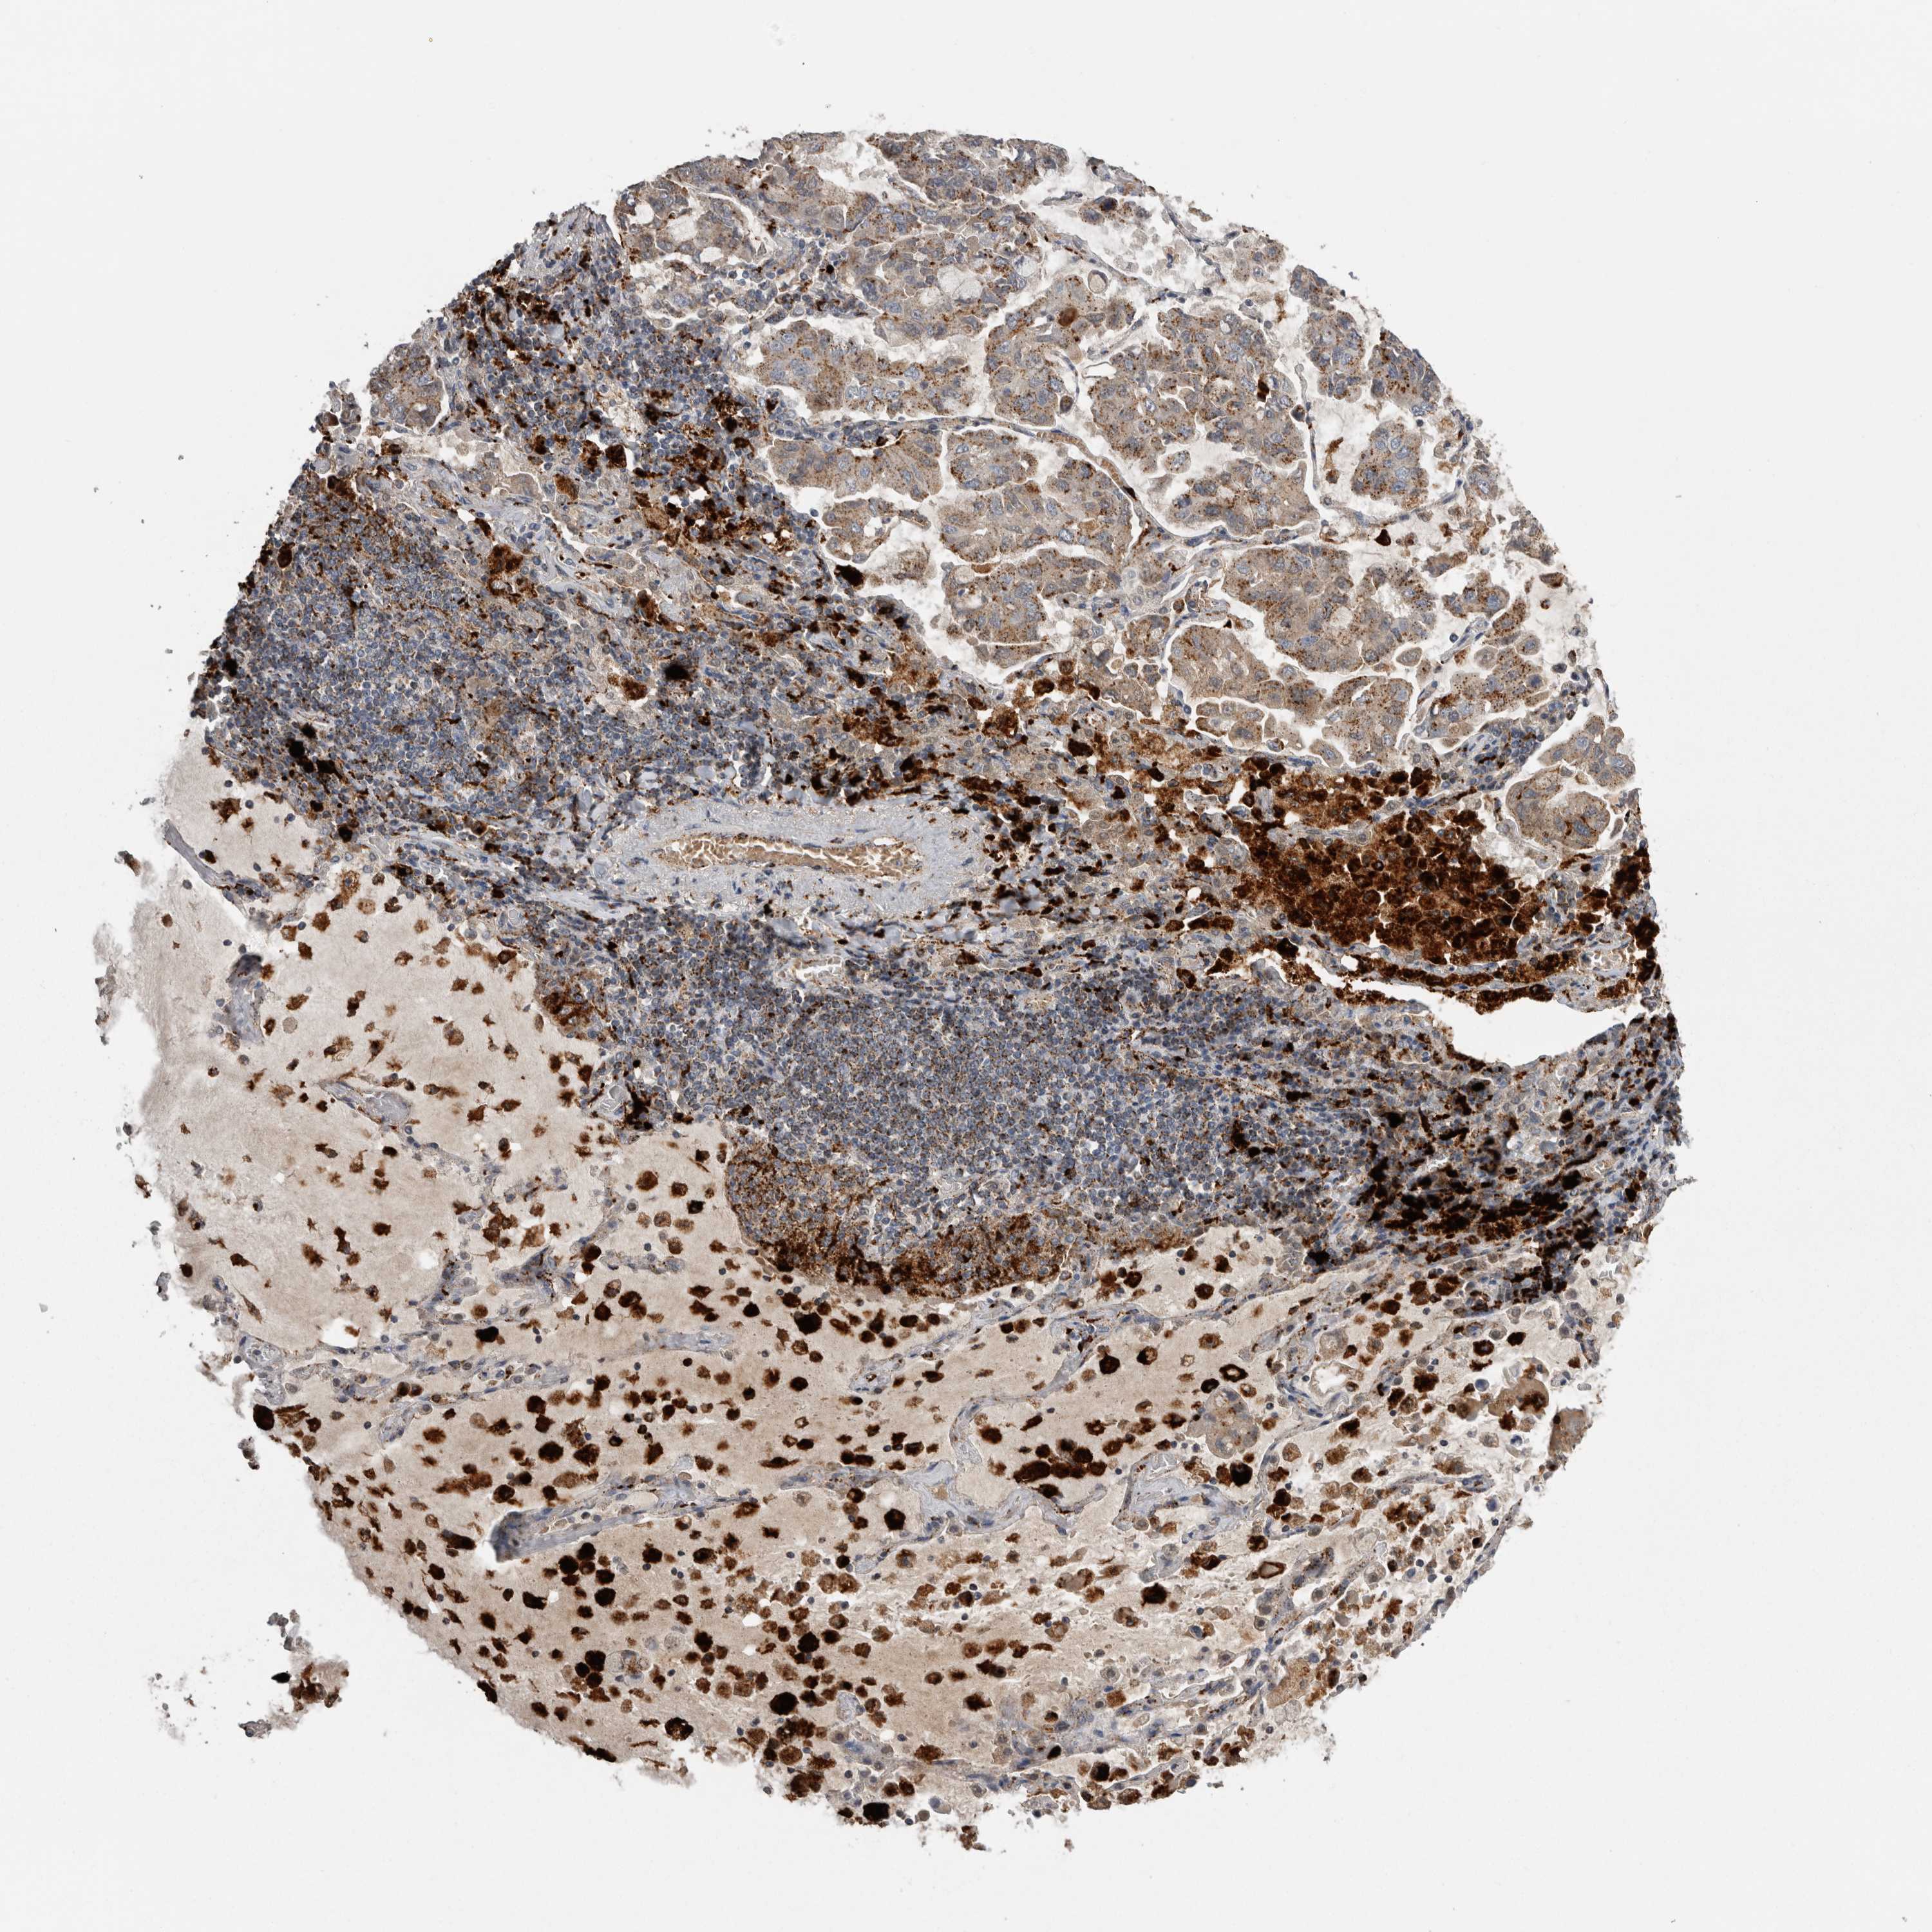

LUNG SQUAMOUS CELL CARCINOMA (TCGA) - Interactive survival scatter ploti

The Survival Scatter plot shows the clinical status (i.e. dead or alive) for all individuals in the patient cohort, based on the same data that underlies the corresponding Kaplan-Meier plots. Patients that are alive at last time for follow-up are shown in blue and patients who have died during the study are shown in red.

The x-axis shows the expression levels (FPKM) of the investigated gene in the tumor tissue at the time of diagnosis. The y-axis shows the follow-up time after diagnosis (years). Both axes are complimented with kernel density curves demonstrating the data density over the axes. The top density plot shows the expression levels (FPKM) distribution among dead (red) and alive patients (blue). The right density plot shows the data density of the survived years of dead patients with high and low expression levels respectively, stratified using the cutoff indicated by the vertical dashed line through the Survival Scatter plot. This cutoff is automatically defined based on the FPKM cutoff that minimizes the p-score. The cutoff can be changed by dragging the vertical line or by entering a cutoff value in the square labeled "Current cut-off".

Under the Survival Scatter plot the p-score landscape (black curve; left axis) is shown together with dead median separation (red curve; right axis). Dead median separation is the difference in median mRNA expression between patients who have died with high and low expression, respectively. It is calculated as follows: median FPKM expression of dead patients with high expression - median FPKM expression of dead patients with low expression. This is intended to aid the user in visually exploring custom cutoffs and the associated p-scores and dead median separation.

Individual patient data is displayed and can be filtered by clicking on one or more of the category buttons on the top of the page. Categories describing expression level and patient information include: high, low, alive, dead, female, male and tumor stages. The scale of the x-axis can be toggled between linear and log-scale by clicking on the "x log" button. Mouse-over function shows TCGA ID, patient information and mRNA expression (FPKM) for each patient.

& Survival analysisi

Kaplan-Meier plots summarize results from analysis of correlation between mRNA expression level and patient survival. Patients were divided based on level of expression into one of the two groups "low" (under cut off) or "high" (over cut off). X-axis shows time for survival (years) and y-axis shows the probability of survival, where 1.0 corresponds to 100 percent.

CTSZ is not prognostic in Lung Squamous Cell Carcinoma (TCGA)

: 255.18

P scorei

N/A

Average pTPM 207.8

Number of samples 489